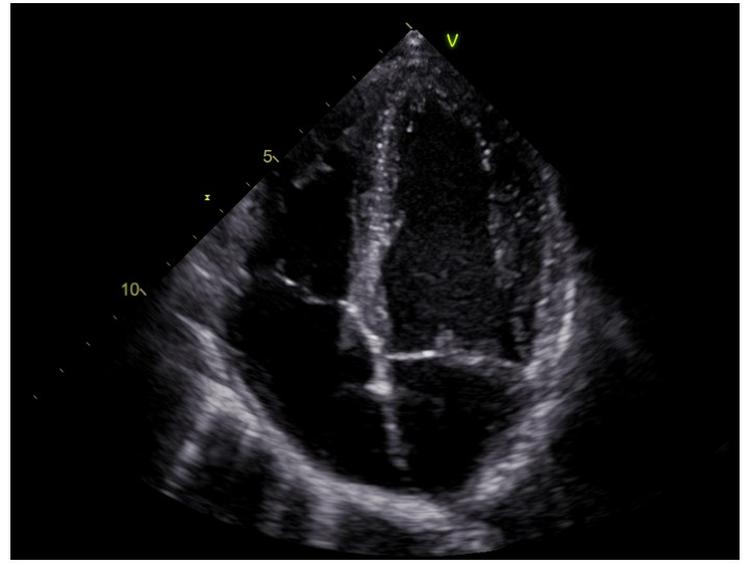

Et hjerte vendt på hovedet på skærmen fra en ultralydskanning. Man kan se de fire hjertekamre, der er opdelt af de hvide vægge, mens det sorte viser blodet, der fyldes op i hjertekamrene. Fra billeder som dette kan hjertelæger forudsige, om patienten får et mildt eller et alvorligt sygdomsforløb.

Nogen påstår, at de kan aflæse din fremtid i dine håndflader. Forskere kan nu, på videnskabelig baggrund, aflæse en covid-19 patients forløb i et ultralydsbillede af patientens hjerte.